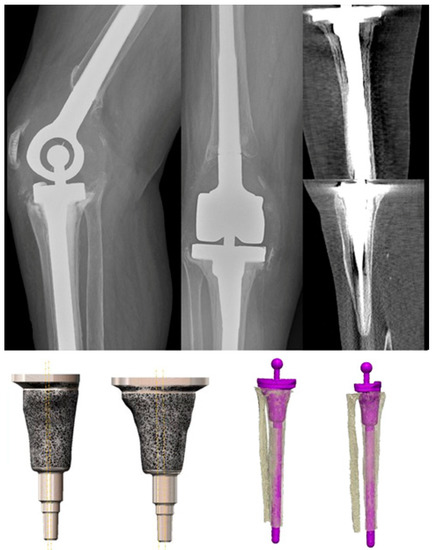

2. Therapy Algorithm and Implant Design

5. Design Adaptations